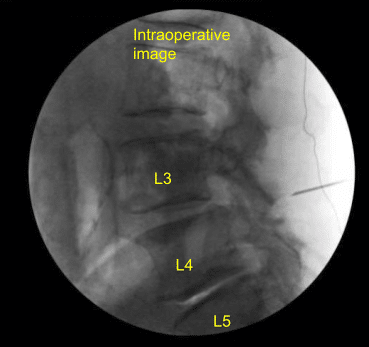

Spinal needle was used to localize the L4-L5 level on the right side. A 1.8-cm linear incision was demarcated and infiltrated with local anesthesia. Skin was opened with a 10-blade scalpel. Hemostasis was obtained with Bovie and Bovie was used to sharply divide the fascia. Sequential dilators were used to dock an 18-mm x 5-cm tubular retractor which was affixed rigidly to the bed frame.